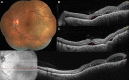

Purpose: To study the incidence and characteristics of bacillary layer detachment (BALAD) occurring with the two most common choroidal malignancies, choroidal metastasis and choroidal melanoma.

Methods: A retrospective multicentric record analysis. Eyes with a diagnosis of choroidal melanoma or choroidal metastasis that had good-quality fundus photography and spectral domain optical coherence tomography (OCT) scans of the macular and tumor regions allowing for delineation of the retinal layers were included for analysis. Qualitative image evaluation was done by two independent graders for the presence, location, and OCT features of BALAD, as well as any associated intraretinal or subretinal fluid. Demographic and clinical data were also retrieved.

Results: Of the 11 eyes with choroidal metastasis and 7 eyes with choroidal melanoma that were included in the final analysis, 6 (54.5%) and 1 (14.3%) had BALAD, respectively. The BALAD co-localized with the subretinal fluid in all cases and with the intraretinal fluid in 1/3 cases (33.3%), was foveal in location in 3 eyes (42.9%), was overlying the tumor in 6 eyes (85.7%), and varied in number and size. Reflectivity within the BALAD was consistently higher than the vitreous and adjacent subretinal fluid, and discernable suspended hyperreflective particles were noted in 5 eyes (71.4%).

Conclusion: BALAD is relatively common with choroidal metastasis. The OCT features described supplement our recognition of this new entity.